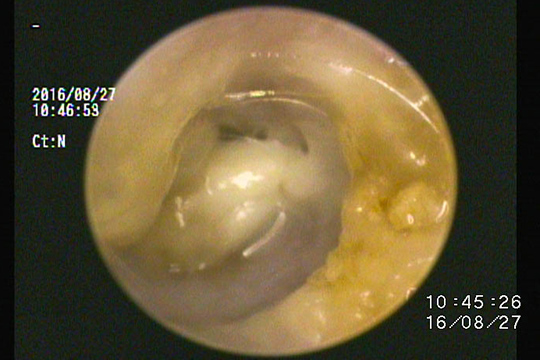

一見綺麗に見えたのですが…鼓膜から水平耳道にかけて毛と耳垢の塊があり、これが痒みの原因になっていました。

このような場合は耳掃除では除去できません。

鉗子を使用して引き出すことが必要です。